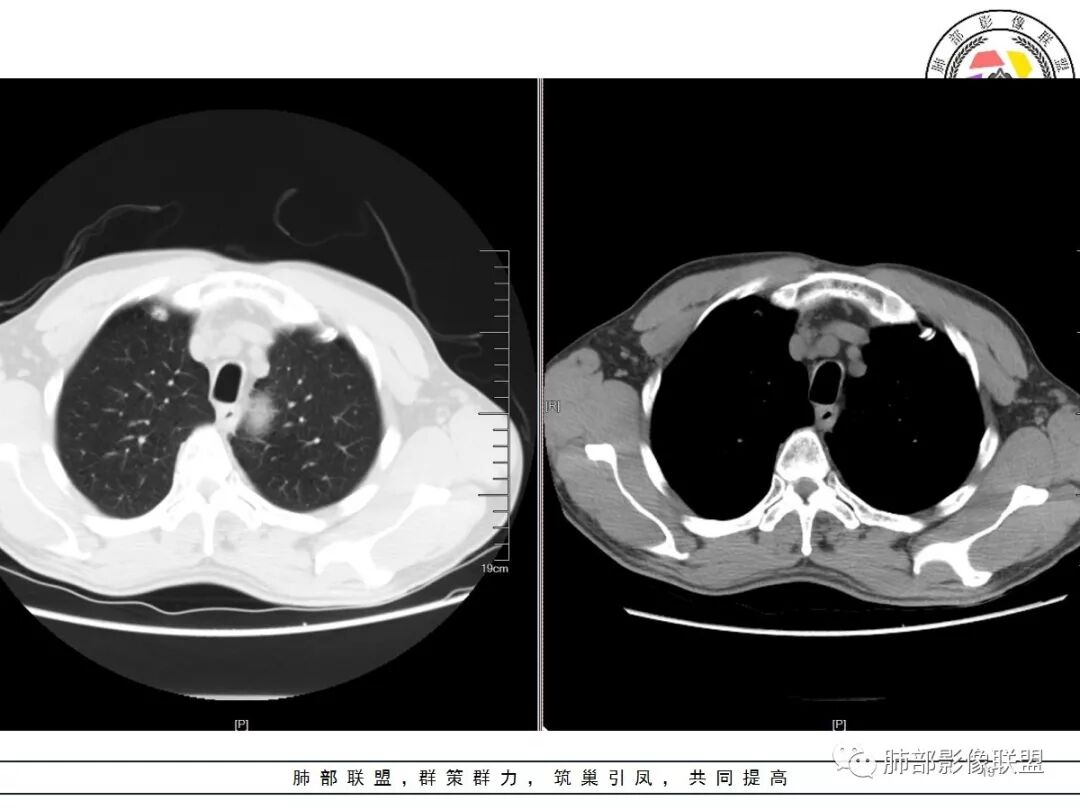

男,57岁,因“体检发现右上肺占位”入院。凝血常规、血常规、肾功能等均未见明显异常。

CT值:

平扫  18                          动脉期  28                      静脉期 41

双肺尖斑片状影及结节影,边缘平直为主,边缘可见胸膜牵拉,考虑结核,鉴别诊断腺癌,本病特点,多灶性,多态性,胸膜牵拉线纤细。

右上肺病灶,边缘平直,有卫星灶,强化不明显,考虑结核可能大

结核。右上肺结节密度均匀轻度强化,结节边缘清晰有小分叶,周围细长软毛刺,有卫星灶。左上肺近纵隔类似片状结节。

右肺尖结节边缘可见卫星灶,结节边缘平直凹陷、长毛刺,外观上有炎性结节的特点

增强扫描右肺尖结节强化不明确,但左肺尖后段结节出现了典型的环形强化